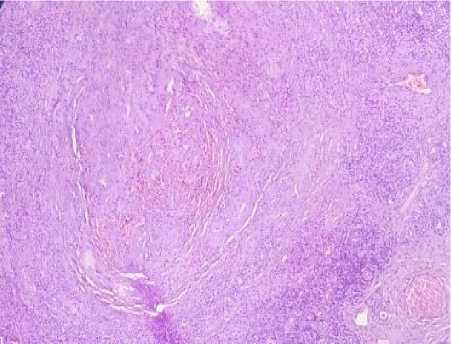

The histopathology examination revealed a gross appearance showed the well encapsulated nodular mass measured 1x1x1 cm with grey to dark brown colour. Under low magnification, it showed a well-encapsulated nodular mass comprising of collagen stromal with lobules of small capillary and cavernous vessels and lymphoid follicle with the germinal center. The vessels were lined by flat to plump endothelial cells with red blood cells within the lumen. Almost half of the nodal parenchyma was effaced by the vascular lesion with the residual lymphoid aggregates underneath the capsule. The lobules of the vascular tumor were separated by collagenous stroma. There were

no areas of necrosis, cytological atypia or any atypical mitotic (Figure 1).

Figure 1. Microscopic appearance with HE stain (40x Magnification).